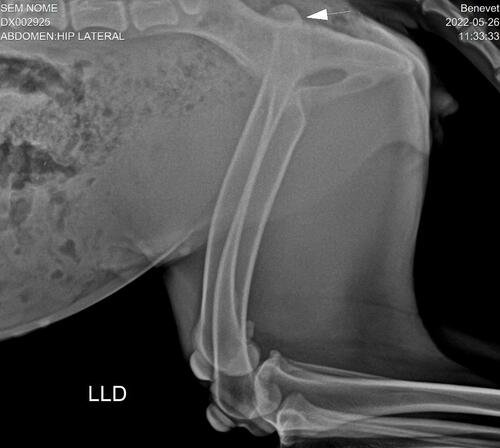

Serena é uma Pastora Belga de Malinois, que infelizmente é mais uma vítima de maus tratos, ela esta desnutrida, com alguns machucados, e além disso, ela também está com a perna luxada, houve um deslocamento da cabeça do fêmur, provavelmente em decorrência de uma batida muito forte! Foi feito um raio-x no hospital veterinário Benevet, e após o diagnostico veterinario, ela precisará fazer uma cirurgia, Sutura Iliofemoral, para colocar o femur no lugar, pois atualmente ela não esta conseguindo apoiar a perna direita no chão!